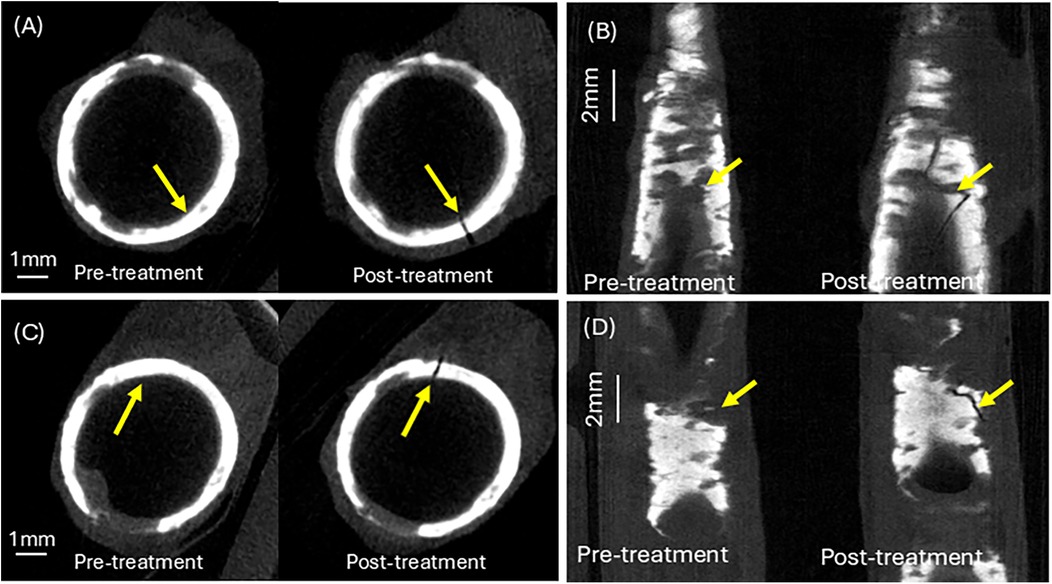

3.4 Calcium plaque cracking

A calcium crack width of greater than 1 mm was observed for both human femoral arteries. Figure 7C shows a top view of the calcium fracture in artery 1. The post-irradiation scan shows the presence of a large crack in calcium, measuring approximately 4 mm. Figure 7D shows a top view of the calcium fracture in artery 2. The calcium fracture in the post-irradiation scan is approximately 3 mm (Table 3).

CT scans in four panels comparing pre-treatment and post-treatment conditions. Panels A and C display cross-sectional views showing circular structures with noticeable changes, marked by yellow arrows. Panels B and D present longitudinal views of bone or similar material with visible changes post-treatment, also indicated by yellow arrows. Panels A and C feature 1 millimeter scale bars, while panels B and D feature 2 millimeter scale bars.

Figure 7. Calcium crack analysis of pre- and post–irradiation micro-CT images. (A) Calcium cracking at the laser irradiation site in artery 1. (B) Calcium cracking at the laser irradiation site in artery 2. (C) Top view of calcium crack at treatment site in artery 1. (D) Top view of calcium crack at treatment site in artery 2. See Supplementary Information for aligned Micro-CT pullback video.